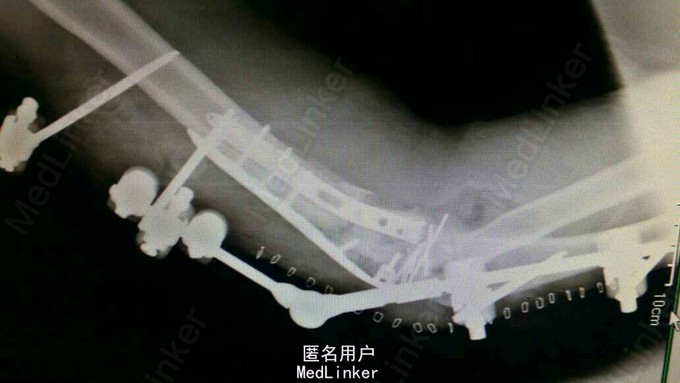

全身多发骨折,右肘关节粉碎性骨折。

对症治疗,消肿后行切开钢板内固定及外固定架固定术。